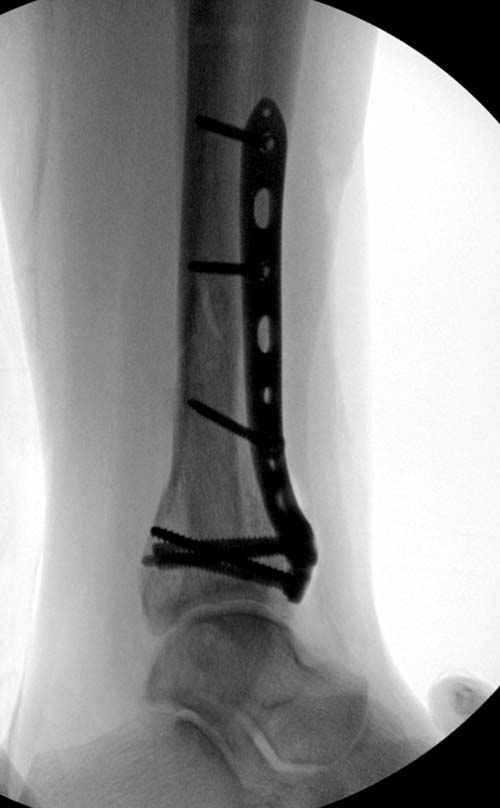

Первый случай, где перелом в результате падения с небольшой высоты, где мортиз рентген снимок показал отстутствие укорочения наружной

лодыжки и КТ срезы подсказали направления атаки. После такой фиксации нет надобности в гипсовой повязке, брейс и через две недели движения в

суставе без нагрузки.